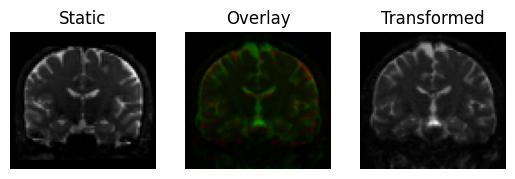

If we look at the result, we can see that this translation is much better than simply aligning the centers of mass

transformed = translation.transform(moving)

<Figure size 640x480 with 3 Axes>

Registration result by translating the moving image, using Mutual Information.